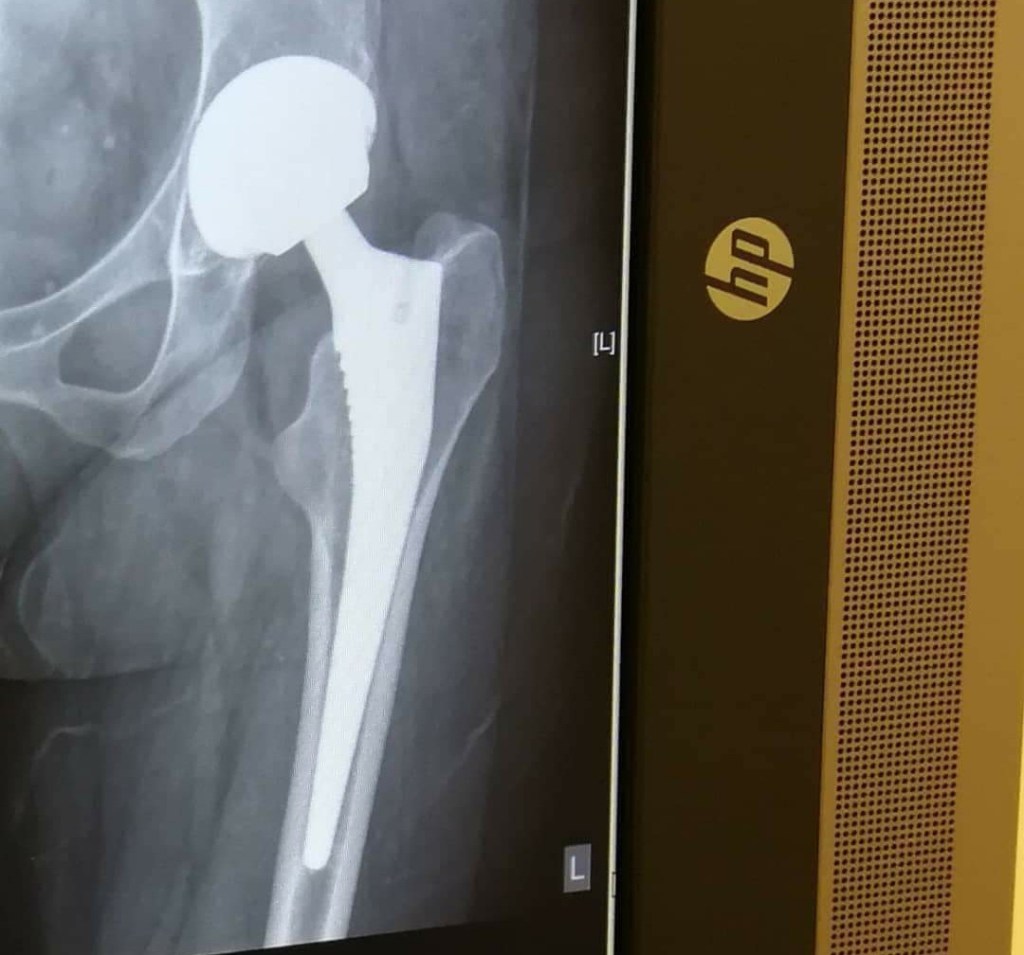

X is for X-Ray

Your rheumatologist will use x-rays to check on the condition of your bones regularly when you have arthritis. You may also need a chest x-ray before being put on certain medications.

- ORTHOPADIC SURGEON – You may never need surgery for your RA. Today’s medicines can stop or slow down the disease. If however there is a lot of joint damage that is affecting your ability to function your rheumatologist may refer you for surgery such as joint replacement. [Web MD]